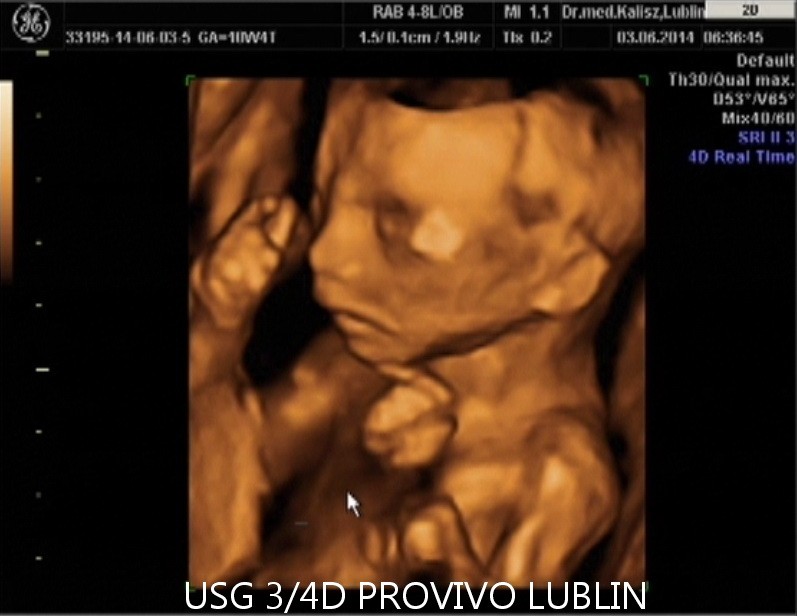

BADANIE USG 3/4D umożliwa dokładny wgląd w rozwój płodu, pozwala na podglądnięcie dziecka w sposób niemalże identyczny z jego aktualnym wyglądem.

W trakcie trwania badania obraz rejestrowany jest na płycie DVD, tak aby każdy przyszły rodzic mógł ponownie odtworzyć badanie w domowym zaciszu. Podczas badania płodu USG 3/4D istnieje również możliwość wydruku zdjęć w formacie kartki pocztowej(148 × 100 mm). Doskonałą jakość, którą charakteryzują się wykonywane przez nas odbitki cyfrowe uzyskujemy dzięki używaniu wyłącznie markowych papierów fotograficznych.